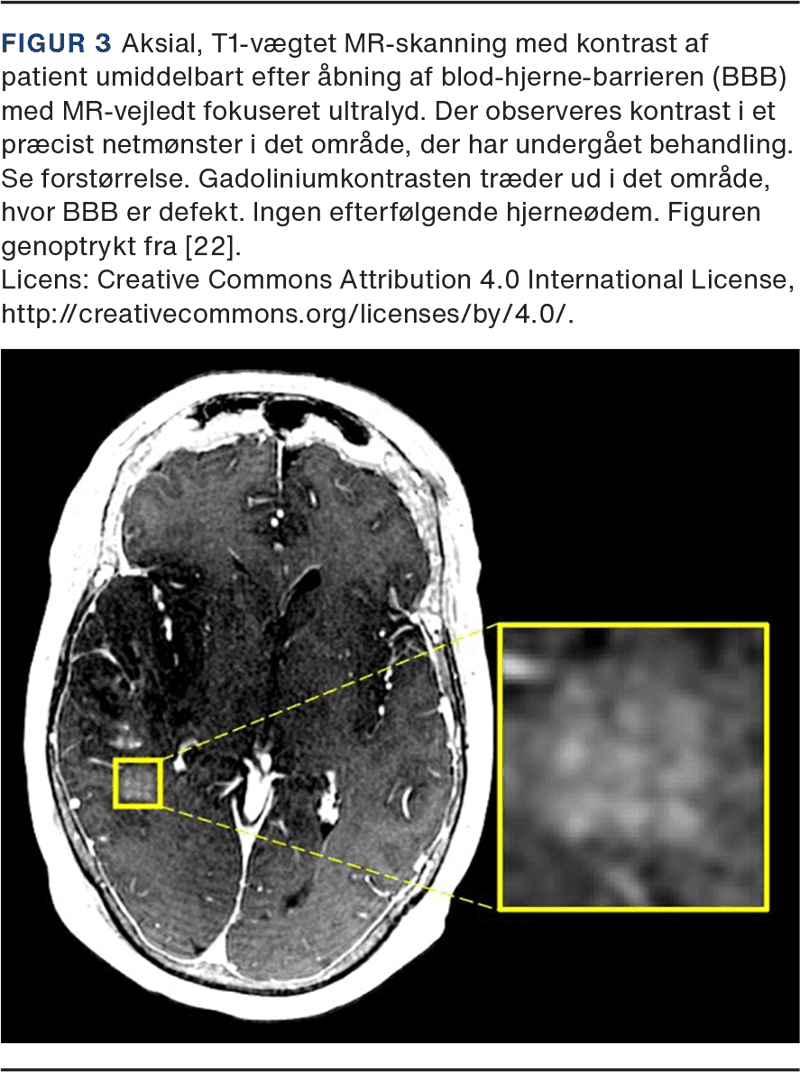

Integriteten af BBB har vist sig at genetableres inden for 6-24 timer. Der er dermed tid til, at de ønskede kemoterapeutika kan nå at passere BBB. Med FUS BBBO har man været i stand til at få dekstranmolekyler (2.000 kDa) til at passere BBB [20], ligesom det har været muligt at skabe transport af forskellige kemoterapeutika, virale vektorer og stam- og immunceller [21]. Selve åbningen af BBB kan valideres med MR med kontrast (Figur 3).